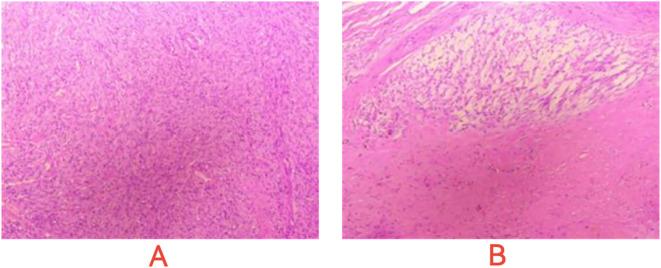

This study reports a 40-year-old male with small intestinal stromal tumor (SIST). After initial surgery and adjuvant imatinib, the tumor recurred. The patient then received multiple rounds of treatment with targeted drugs and surgical interventions. Through comprehensive analysis of gene mutation profiles (KIT and HRR gene mutations, including BRCA2), a combination therapy of fluzoparib, pamiparib, and ripretinib was administered, stabilizing the patient's condition with significant efficacy. This case highlights the importance of genetic testing and personalized targeted treatment strategies for gastrointestinal stromal tumor (GIST) patients.

摘要

本研究报告了一名40岁患有小肠间质瘤(SIST)的男性。在初次手术及辅助使用伊马替尼后,肿瘤复发。该患者随后接受了多轮靶向药物治疗及手术干预。通过对基因突变谱(KIT和HRR基因突变,包括BRCA2)的综合分析,给予氟唑帕利、帕米帕利和瑞派替尼联合治疗,显著稳定了患者病情,疗效显著。该病例突出了基因检测及针对胃肠间质瘤(GIST)患者的个性化靶向治疗策略的重要性。